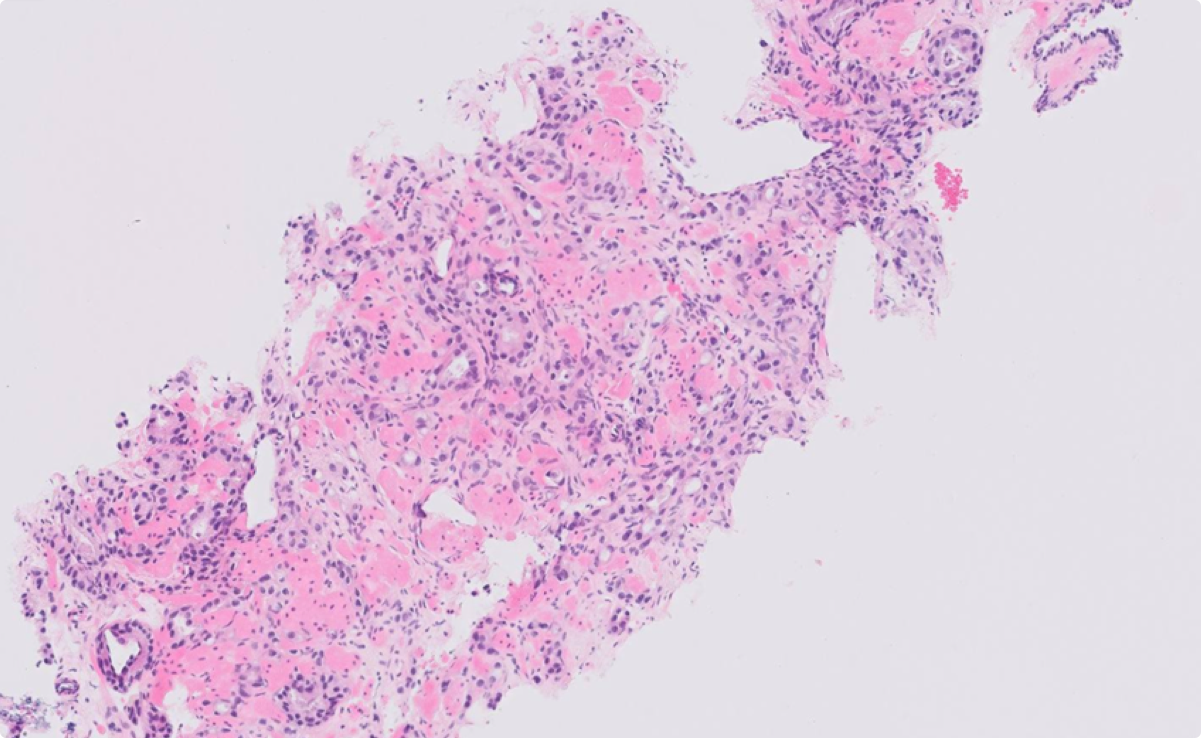

Gleason heatmap

Perineural invasion heatmap